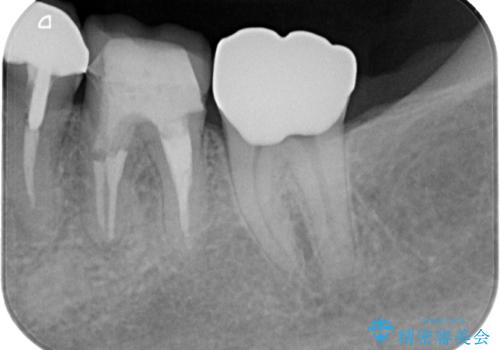

- 左右ともに下顎の奥歯に違和感や痛みを感じるとのことで来院された患者様です。

左下奥歯は詰め物と周辺の歯が欠けて、しみている状態でした。

部分的な詰め物ですと、再度破損リスクが高いため、高強度のセラミッククラウンにて補綴治療を行うこととしました。

また、親知らずが埋もれており、よい機会なので抜歯を行ってからセラミッククラウンを装着することとしました。

治療から9か月ほどが経過した時点で、違和感や痛みはなく、歯根端切除術を行った右下は、レントゲンでも良好な経過が確認できました。